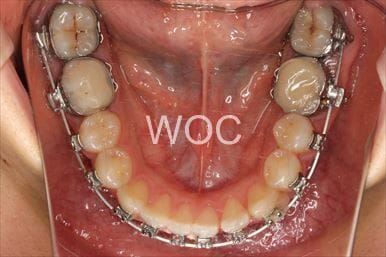

治療中1

治療中2

治療中3

治療中4

治療中5

- 年齢:17歳女性

- 主訴:出っ歯、前歯のガタガタが気になる

- 基本矯正料金:78万円

- 治療期間:1年2ヶ月

- 抜歯部位:上顎両側第一小臼歯